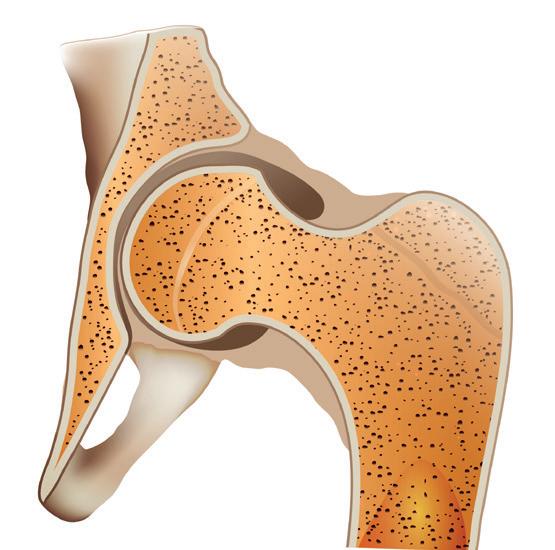

STRUTTURA DELL’OSSO

Midollo osseo giallo

Cavità midollare

Cartilagine

Vasi sanguigni

Periostio

Osso compatto

Osso spugnoso

Linea epifisaria

Midollo osseo rosso

L’interno dell’osso è costituito da una struttura spugnosa (osso cancelloso) composta da sottili perle ossee a forma di reticolo (le cosiddette trabecole). L’osso cancelloso contribuisce a risparmiare sostanza ossea e quindi a ridurre il peso dell’osso e si trova principalmente alle estremità delle ossa lunghe, oltre che nelle costole, nel cranio e nelle vertebre.

Contiene il midollo osseo rosso, in cui si formano le cellule del sangue, e il midollo osseo giallo, ricco di cellule grasse.